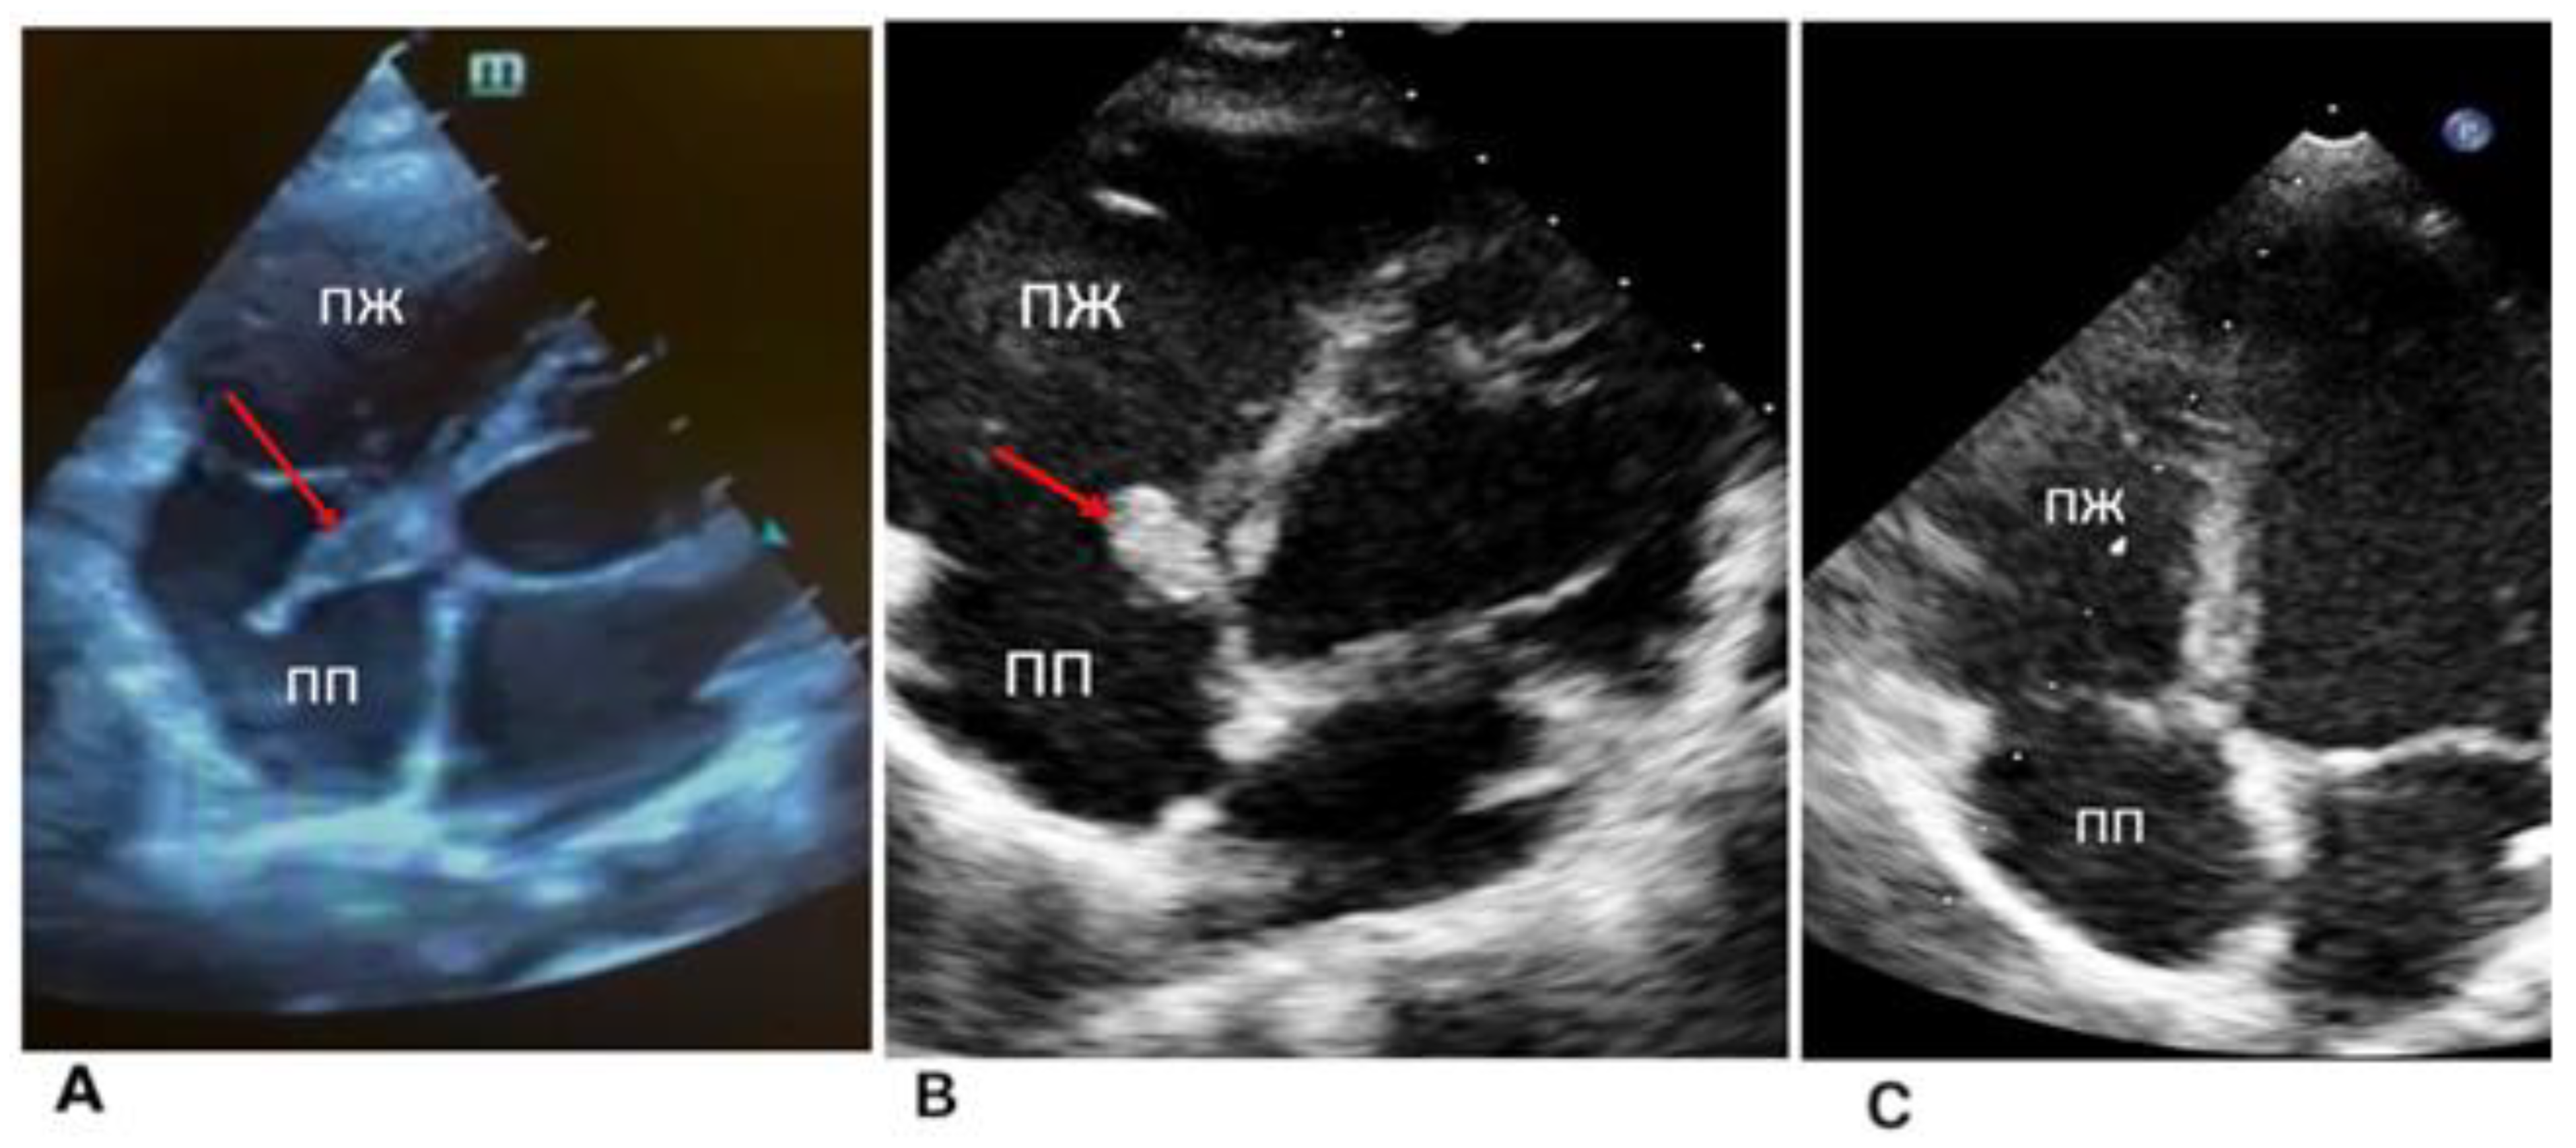

Echocardiography (ECG) and 24 h ECG monitoring revealed no rhythm and conduction disturbances, and no ischemic changes were registered (Figure 1).

Figure 1.

Echocardiography (dynamics of thrombus regression). (A) Thrombus was in the septal leaflet of the tricuspid valve (red arrow) upon admission, size 16 × 6.5 mm. (B) Two weeks after the start of anticoagulant therapy. The red arrow indicates a thrombus with dimensions of 12.5 × 7 mm. (C) Lysis of a thrombus in the septal leaflet.

Applying echocardiography data, prolapse in the diastole cavity of the right ventricle was revealed. The projection of the tricuspid valve leaflets, a homogeneous formation with fuzzy contours, 16 × 6.5 mm in size, on a wide base were examined (Figure 1A).

The dimensions of the heart were not enlarged, and the contractility of the right and left ventricles were preserved. The condition was regarded as the course of infective endocarditis of an unspecified etiology with tricuspid valve damage.

During echocardiography, the formation of a tricuspid septal leaflet on a wide base, and a thrombus could not be ruled out. It was clearly visualized with even edges (12.5 × 7 mm in size) and a tricuspid septal leaflet was not floating. The biomechanics of the valve were not impacted. The dimensions of the heart chambers were normal and myocardial contractility was preserved; however, basal lower septal segment dyskinesia was detected (Figure 1B).